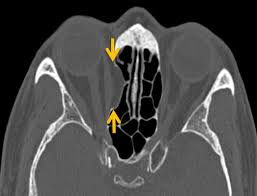

O – Onodi cell – if present, to assess its relationship to optic nerve, ICA, dehiscence (coronal and axial) and presence of horizontal septa.